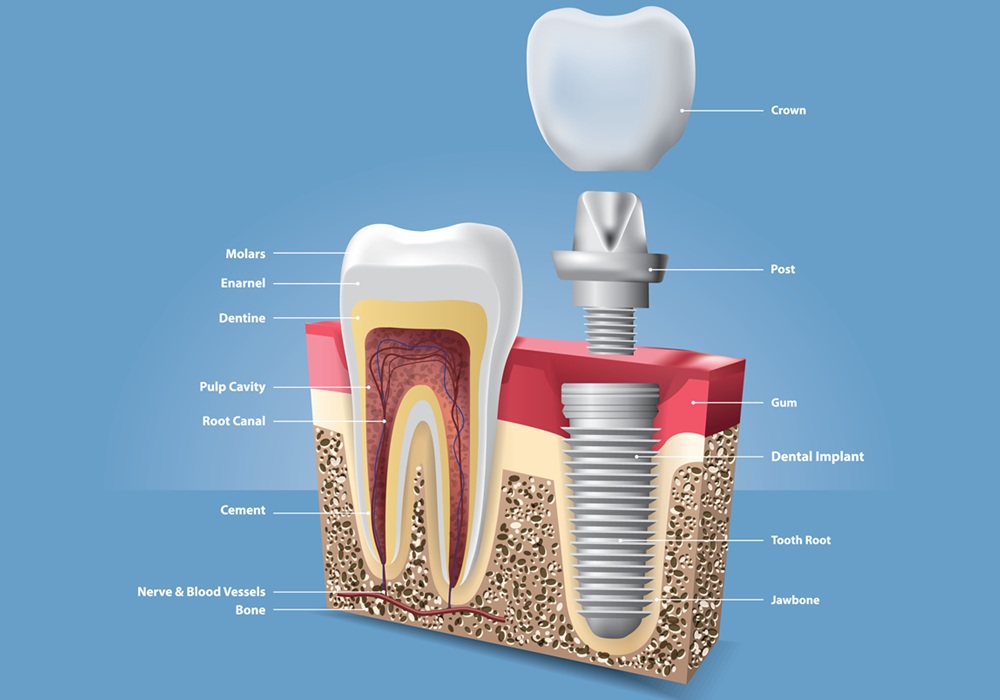

インプラント

インプラントは、失った歯の代わりに人工の歯根を埋め込み、その上に人工の歯をのせて噛めるようにする治療です。当院では、まずCT撮影を行い、骨の量や位置を細かく確認したうえで、安全に進められるか丁寧に判断します。治療は痛みや負担をできるだけ抑えることを心がけ、患者さんの体調や生活に合わせて無理のない計画を立てます。また、治療後のメンテナンスがとても大切なため、日常のケア方法もわかりやすくお伝えします。しっかり噛める喜びを長く保てるよう、術後のサポートまで含めて支えることを大切にしています。